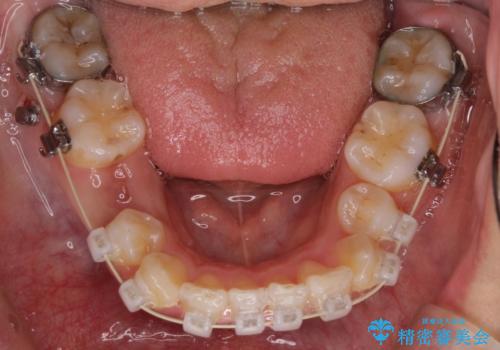

- 矯正装置

- クリアブラケット

上顎両側と左下の前から4番目の歯と、右下の乳歯を抜歯して矯正することとなりました。